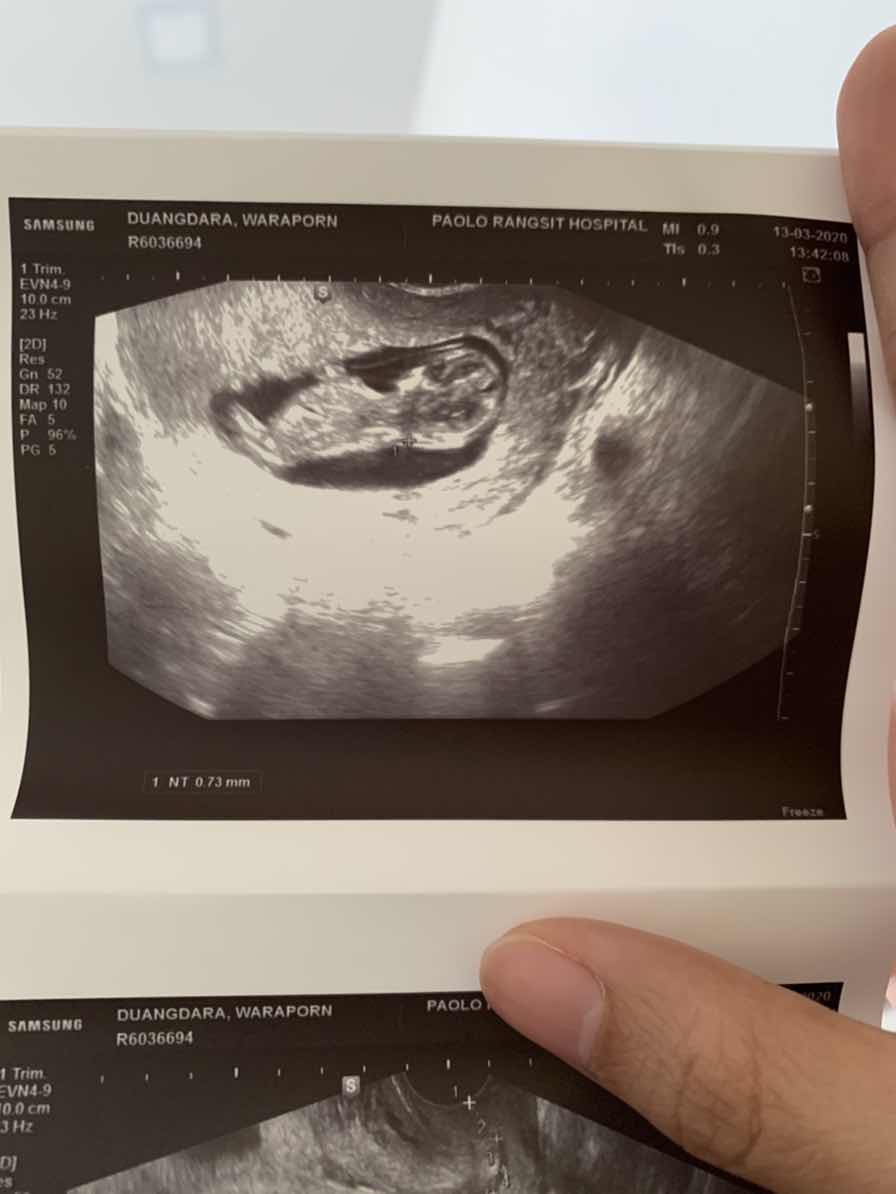

ตอน11+2วันคะ